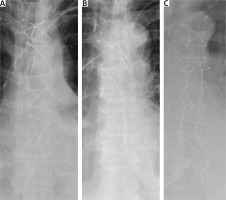

In the defined method, the sternum is closed with standard 5 mm/45 cm surgical stainless steel sternal wires (Doğsan, Trabzon/Turkey) as in the “figure of 8”. However, the wires are knotted laterally with the corresponding previous one sequentially on the lateral side of the sternum rather than midline knotting as in the “figure of 8” (Figures 1 A–C, 2 A, B). The name comes from the surgical view of wires when the sternum is closed. The wires are in the form of “/” (Figure 3).

Figure 1

Schematic wiring order: A – sternal wires are applied in order from a to d, B – in “figure of 8” wiring “a”s are knotted with “d”s, C – in “/” wiring, each “a” is knotted with the next “a”, and each “d” is knotted with the next “d”